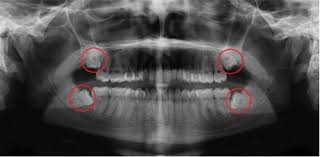

Wisdom Teeth Surgery How Is It Done And What To Do After

Wisdom Teeth Surgery How Is It Done And What To Do After from www.missionimplantcenter.com